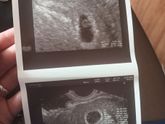

Волновалась весь день сегодня, узи было назначено на 14-20, в кабинет я попала только в 15-40? оказывается даже в платной клинике мы должны были сидеть в живой очереди ? ну да ладно. Не в этом суть.

Самое главное, что все хорошо, сначала эмбриончика … Читать далее